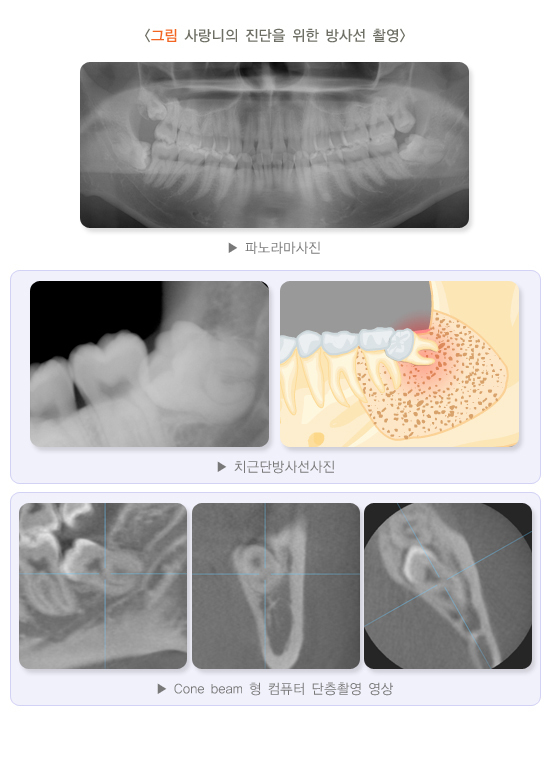

5. 사랑니의 진단을 위한 방사선 촬영

치과용 엑스레이는 전체 치아 및 턱뼈의 전반적인 평가가 필요할 때 찍는 파노라마 사진과 치아 한두 개를 잘 관찰하기 위해 찍는 치근단방사선 사진이 있습니다. 아래턱 사랑니 치근 아래쪽으로 하치조 신경이 포함된 하악관이 지나가는데 파노라마 사진을 통해 하악관의 대략적인 위치와 사랑니를 포함한 전체 치아 및 잇몸뼈의 상태를 평가할 수 있습니다.

아래턱 사랑니가 신경관에 아주 근접해 있다면 발치 후 일시적으로 하치조 신경이 분포하는 아래 입술 및 아래턱, 아래 앞니와 잇몸에 감각이 둔화될 수 있습니다. 이때는 치과의사와 상의하여 치과용 컴퓨터단층사진(CT) 촬영 여부를 결정하고 사랑니와 하악관의 관계를 보다 정확하게 평가한 후 발치를 결정하는 것이 좋습니다.